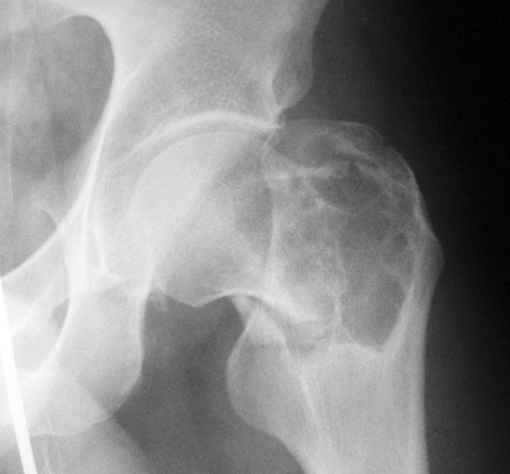

Уважаемые коллеги! Больной (1974 г.р.) травма 26.01.2009г., у пал на ра-боте с высоты своего роста, доставлен в одну из горбольниц Екатеринбурга в травматологическое отделение. На рентгенограмме выявлен патологический перелом чрезвертельной области левого бедра.

Доброкачественная опухоль (ОБК?, энхондрома?), по данным RS. Дополнительно произведено КТ. Наложено скелетное вытяжение.

Прилагаются: рентгенограмма и данные СТ

По данным рентгенограммы и СТ диагноз определить в данном случае нельзя. При дифдиагнозе можно предполагать костную кисту, остеокластому, хондрому; в нашей клинике был подобный случай - гистологически верифицирована хондромиксоидная фиброма.